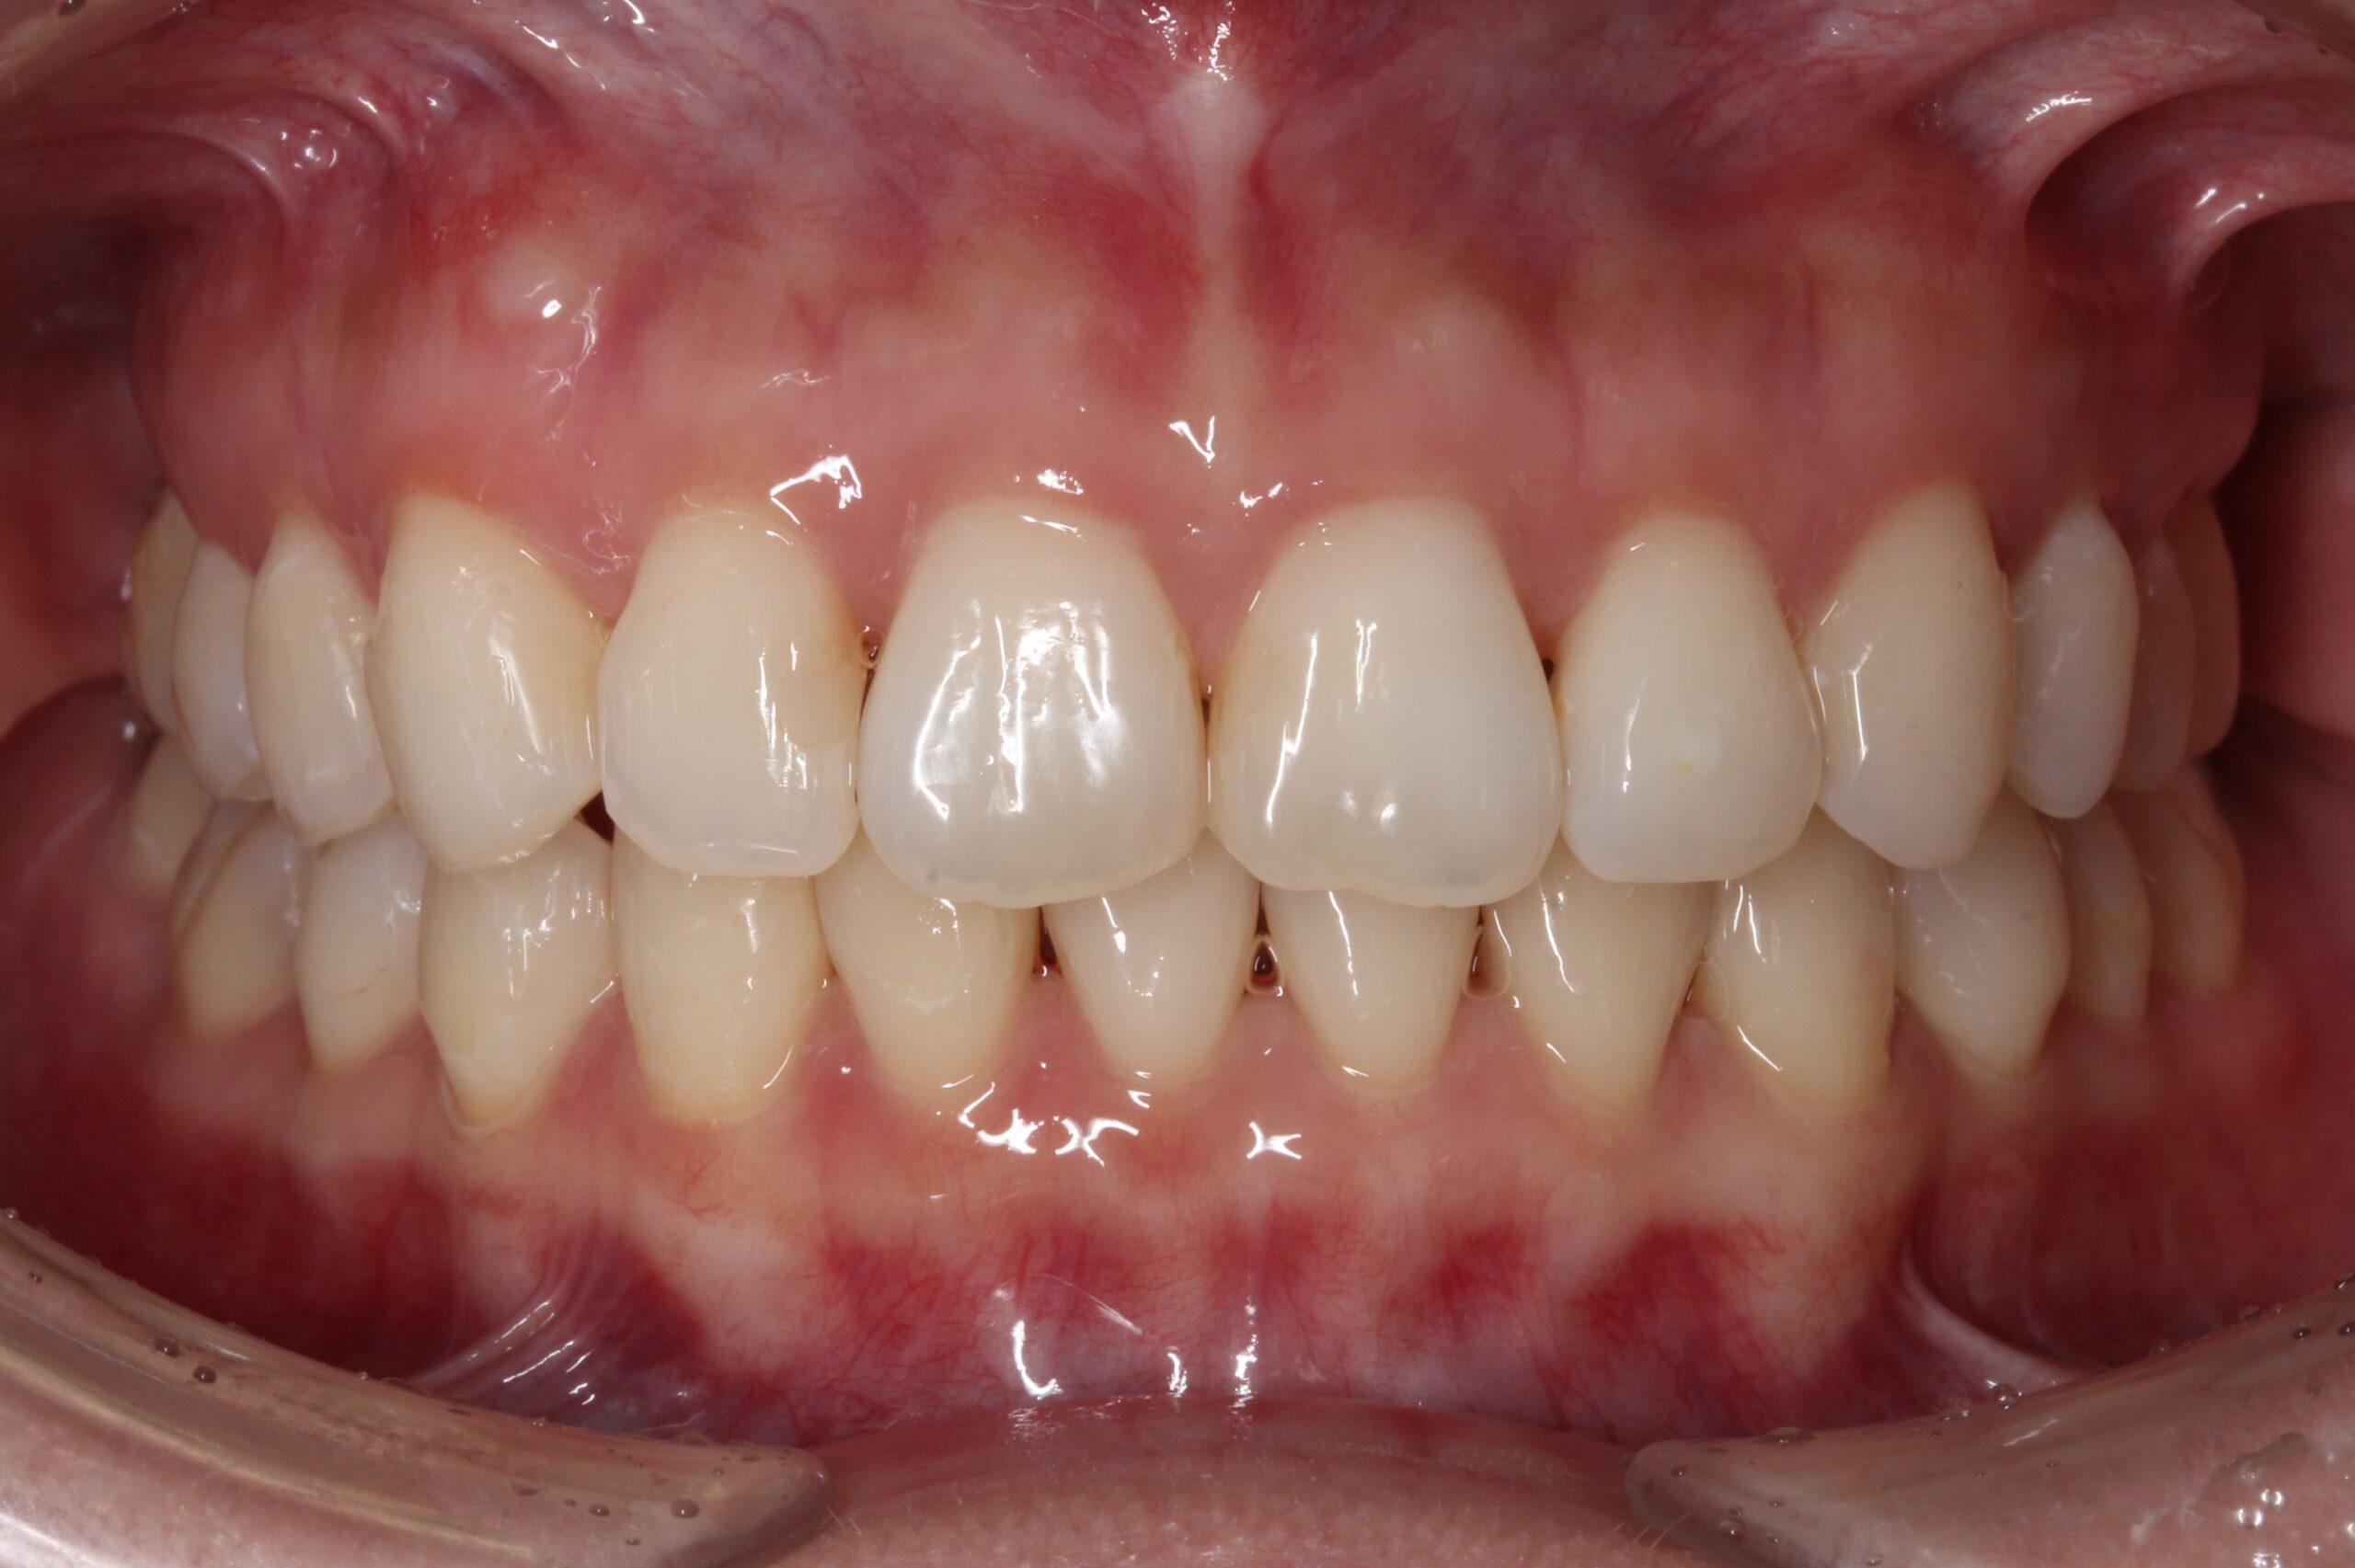

矯正術前:正面

矯正術後:正面